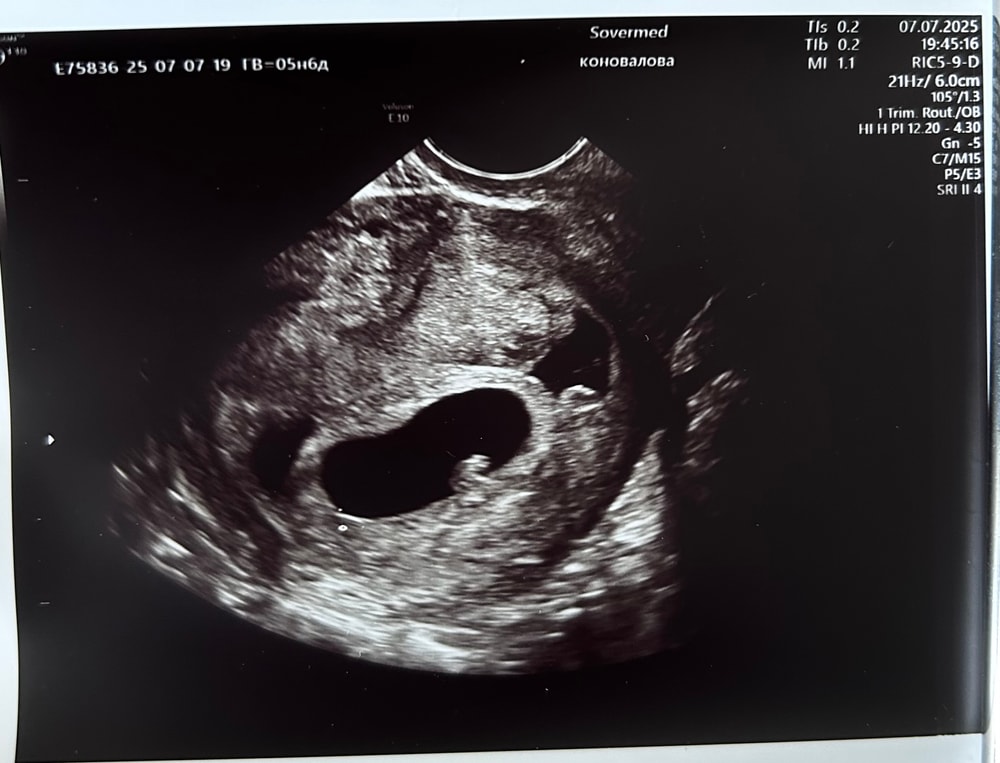

УЗИ, КТГ, доплерДевочки, кто понимает, не дает мне покоя штучка справа, рядом с пя, что это может быть? В заключении написано 1 плодное яйцо, врач мне не особо понравилась, была грубовата и немногословна

Мне с такой наподобие картинкой во время 4й беременности на 8й неделе предположила гематому или неразвившуюся вторую беременность. Через 2 недели назначили контрольное ухи, всё исчезло.

Ксения, это узи было в платной, хорошей вроде как, клинике, если это второе пя, оно почему-то не ровное, да и как она тогда могла не сказать, даже в заключении написала, что одно. И не опасно ли делать слишком часто узи? 6.3 недель, было уже 3 узи